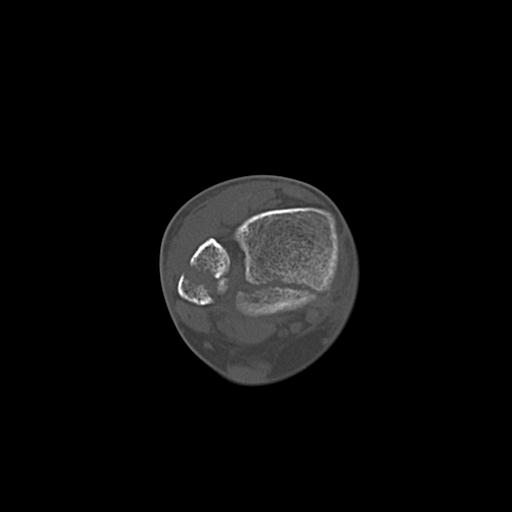

102755 1/4 2R 1/15 2R 右足関節 68歳女性 右三果脱臼骨折